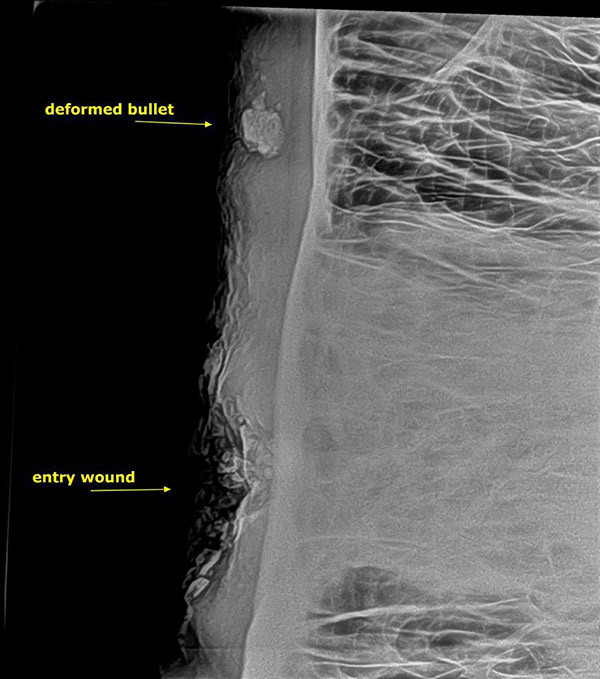

Elefantens hoved blev røntgenfotograferet. Billedet afslørede dyrets afsindige held. Havde kuglen ramt blot et par centimeter længere nede, var den sandsynligvis død.